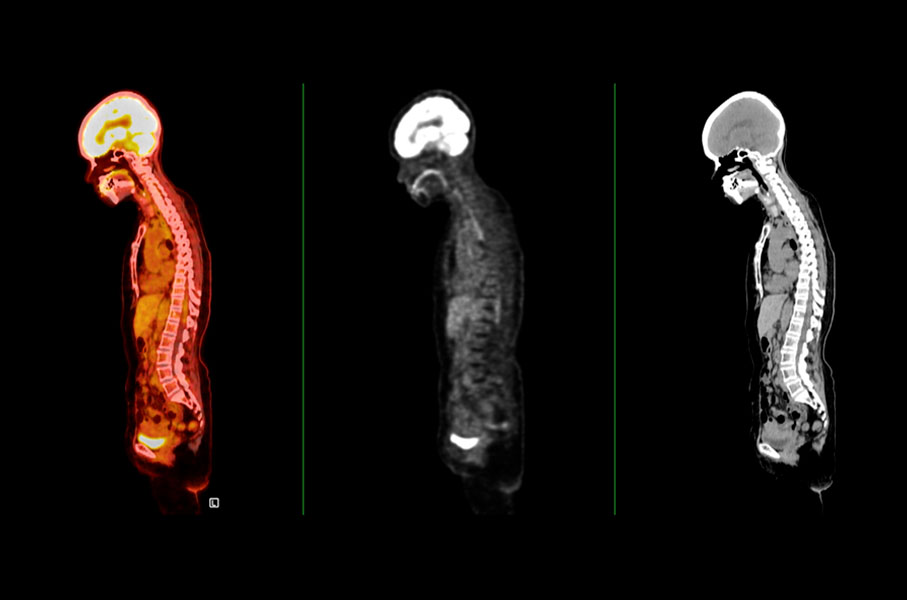

A NBR IEC 61675-1 de 11/2025 - Dispositivos de imagem por radionuclídeos — Características e condições de ensaio - Parte 1: Tomógrafos por emissão de pósitron especifica a terminologia e os métodos de ensaio para declarar as características dos tomógrafos por emissão de pósitrons. Os tomógrafos por emissão de pósitrons detectam a radiação de aniquilação de radionuclídeos emissores de pósitrons por detecção de coincidência.

Os desenvolvimentos posteriores de tomógrafos por emissão de pósitrons permitiram que a maioria dos tomógrafos seja operada no modo de aquisição totalmente 3D. Para conformidade com esta tendência, este documento descreve as condições de ensaio de acordo com esta característica de aquisição. Além disso, hoje, um tomógrafo por emissão de pósitrons geralmente inclui equipamento de raios x para tomografia computadorizada (TC). Para este documento, os dispositivos híbridos PET-CT são considerados estado da arte, e os tomógrafos por emissão de pósitrons dedicados que não incluem o componente de raios X são apenas casos especiais.

Embora os métodos de ensaio especificados sejam otimizados para o componente positron emission tomographs (PET) de dispositivos híbridos PET-CT, eles também podem ser utilizados para o componente PET de dispositivos híbridos PET-RM. Os métodos de ensaio especificados neste documento foram selecionados para refletir, tanto quanto possível, o uso clínico de tomógrafos por emissão de pósitrons.